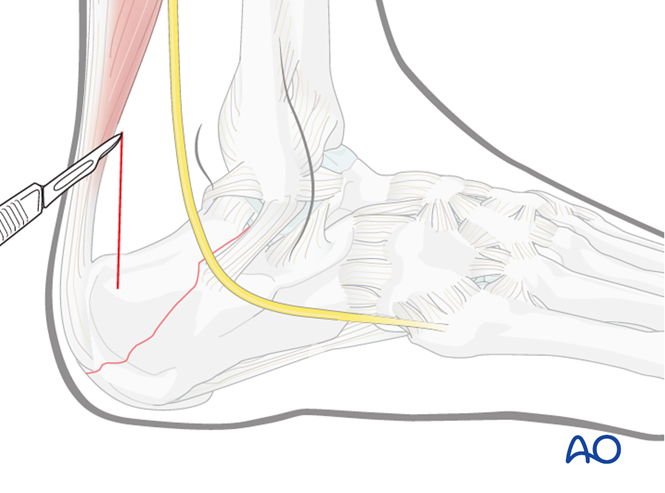

可采用跟骨后方微创后侧入路:27.跟骨后方的微创入路(AO官网版)

图片

sural nerve腓肠神经

small saphenous vein小隐静脉